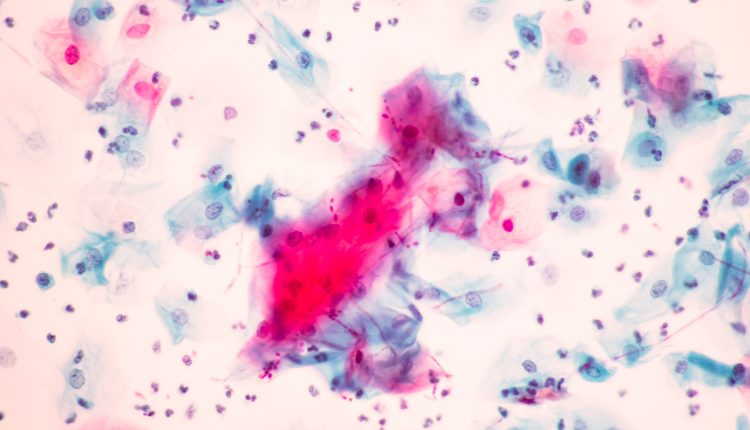

Η Νέα Υόρκη βρίσκεται αντιμέτωπη με μια αυξανόμενη απειλή δημόσιας υγείας, καθώς επικίνδυνοι μικροοργανισμοί, γνωστοί ως «superbugs», εξαπλώνονται και παρουσιάζουν ανθεκτικότητα στις υπάρχουσες θεραπείες. Ανάμεσά τους, ο μύκητας Candida auris προκαλεί ιδιαίτερη ανησυχία, καθώς επιβιώνει σε επιφάνειες ακόμη και μετά τον καθαρισμό, συχνά δεν ανταποκρίνεται στις συνήθεις αντιμυκητιασικές θεραπείες και μπορεί να οδηγήσει σε θανατηφόρες λοιμώξεις του αίματος.

Η πολιτεία της Νέας Υόρκης καταγράφει σταθερή αύξηση των περιστατικών Candida auris από το 2016, όταν και ανιχνεύθηκε επίσημα για πρώτη φορά. Μόνο το περασμένο έτος, καταγράφηκαν 623 κλινικά περιστατικά, δηλαδή ασθενείς που νόσησαν, καθώς και 849 περιστατικά επιτήρησης, που αφορούν άτομα τα οποία βρέθηκαν θετικά στον μύκητα χωρίς να εμφανίζουν συμπτώματα.

Σύμφωνα με μελέτη του προηγούμενου έτους, η μητροπολιτική περιοχή Νέας Υόρκης/Νιου Τζέρσεϊ αντιστοιχεί σχεδόν στο 20% των συνολικών περιστατικών Candida auris στις Ηνωμένες Πολιτείες. Οι ερευνητές εντόπισαν ως βασική αιτία της αύξησης τα υψηλά επίπεδα ταξιδιών και εμπορίου με τη Νότια Ασία.

Παρά την ανησυχητική εικόνα, υπάρχουν και ενθαρρυντικά στοιχεία. Αν και το Candida auris έχει γίνει πιο διαδεδομένο στη Νέα Υόρκη, μεταδίδεται κυρίως σε δομές υγειονομικής περίθαλψης, όπως οίκοι ευγηρίας και νοσοκομεία. Ο Δρ Γκλατ διευκρίνισε ότι δεν αποτελεί σοβαρή απειλή για τον μέσο πολίτη, αλλά είναι ιδιαίτερα επικίνδυνο για ασθενείς σε τέτοιες δομές, ειδικά για όσους λαμβάνουν πολλαπλά αντιβιοτικά ή είναι ανοσοκατεσταλμένοι.